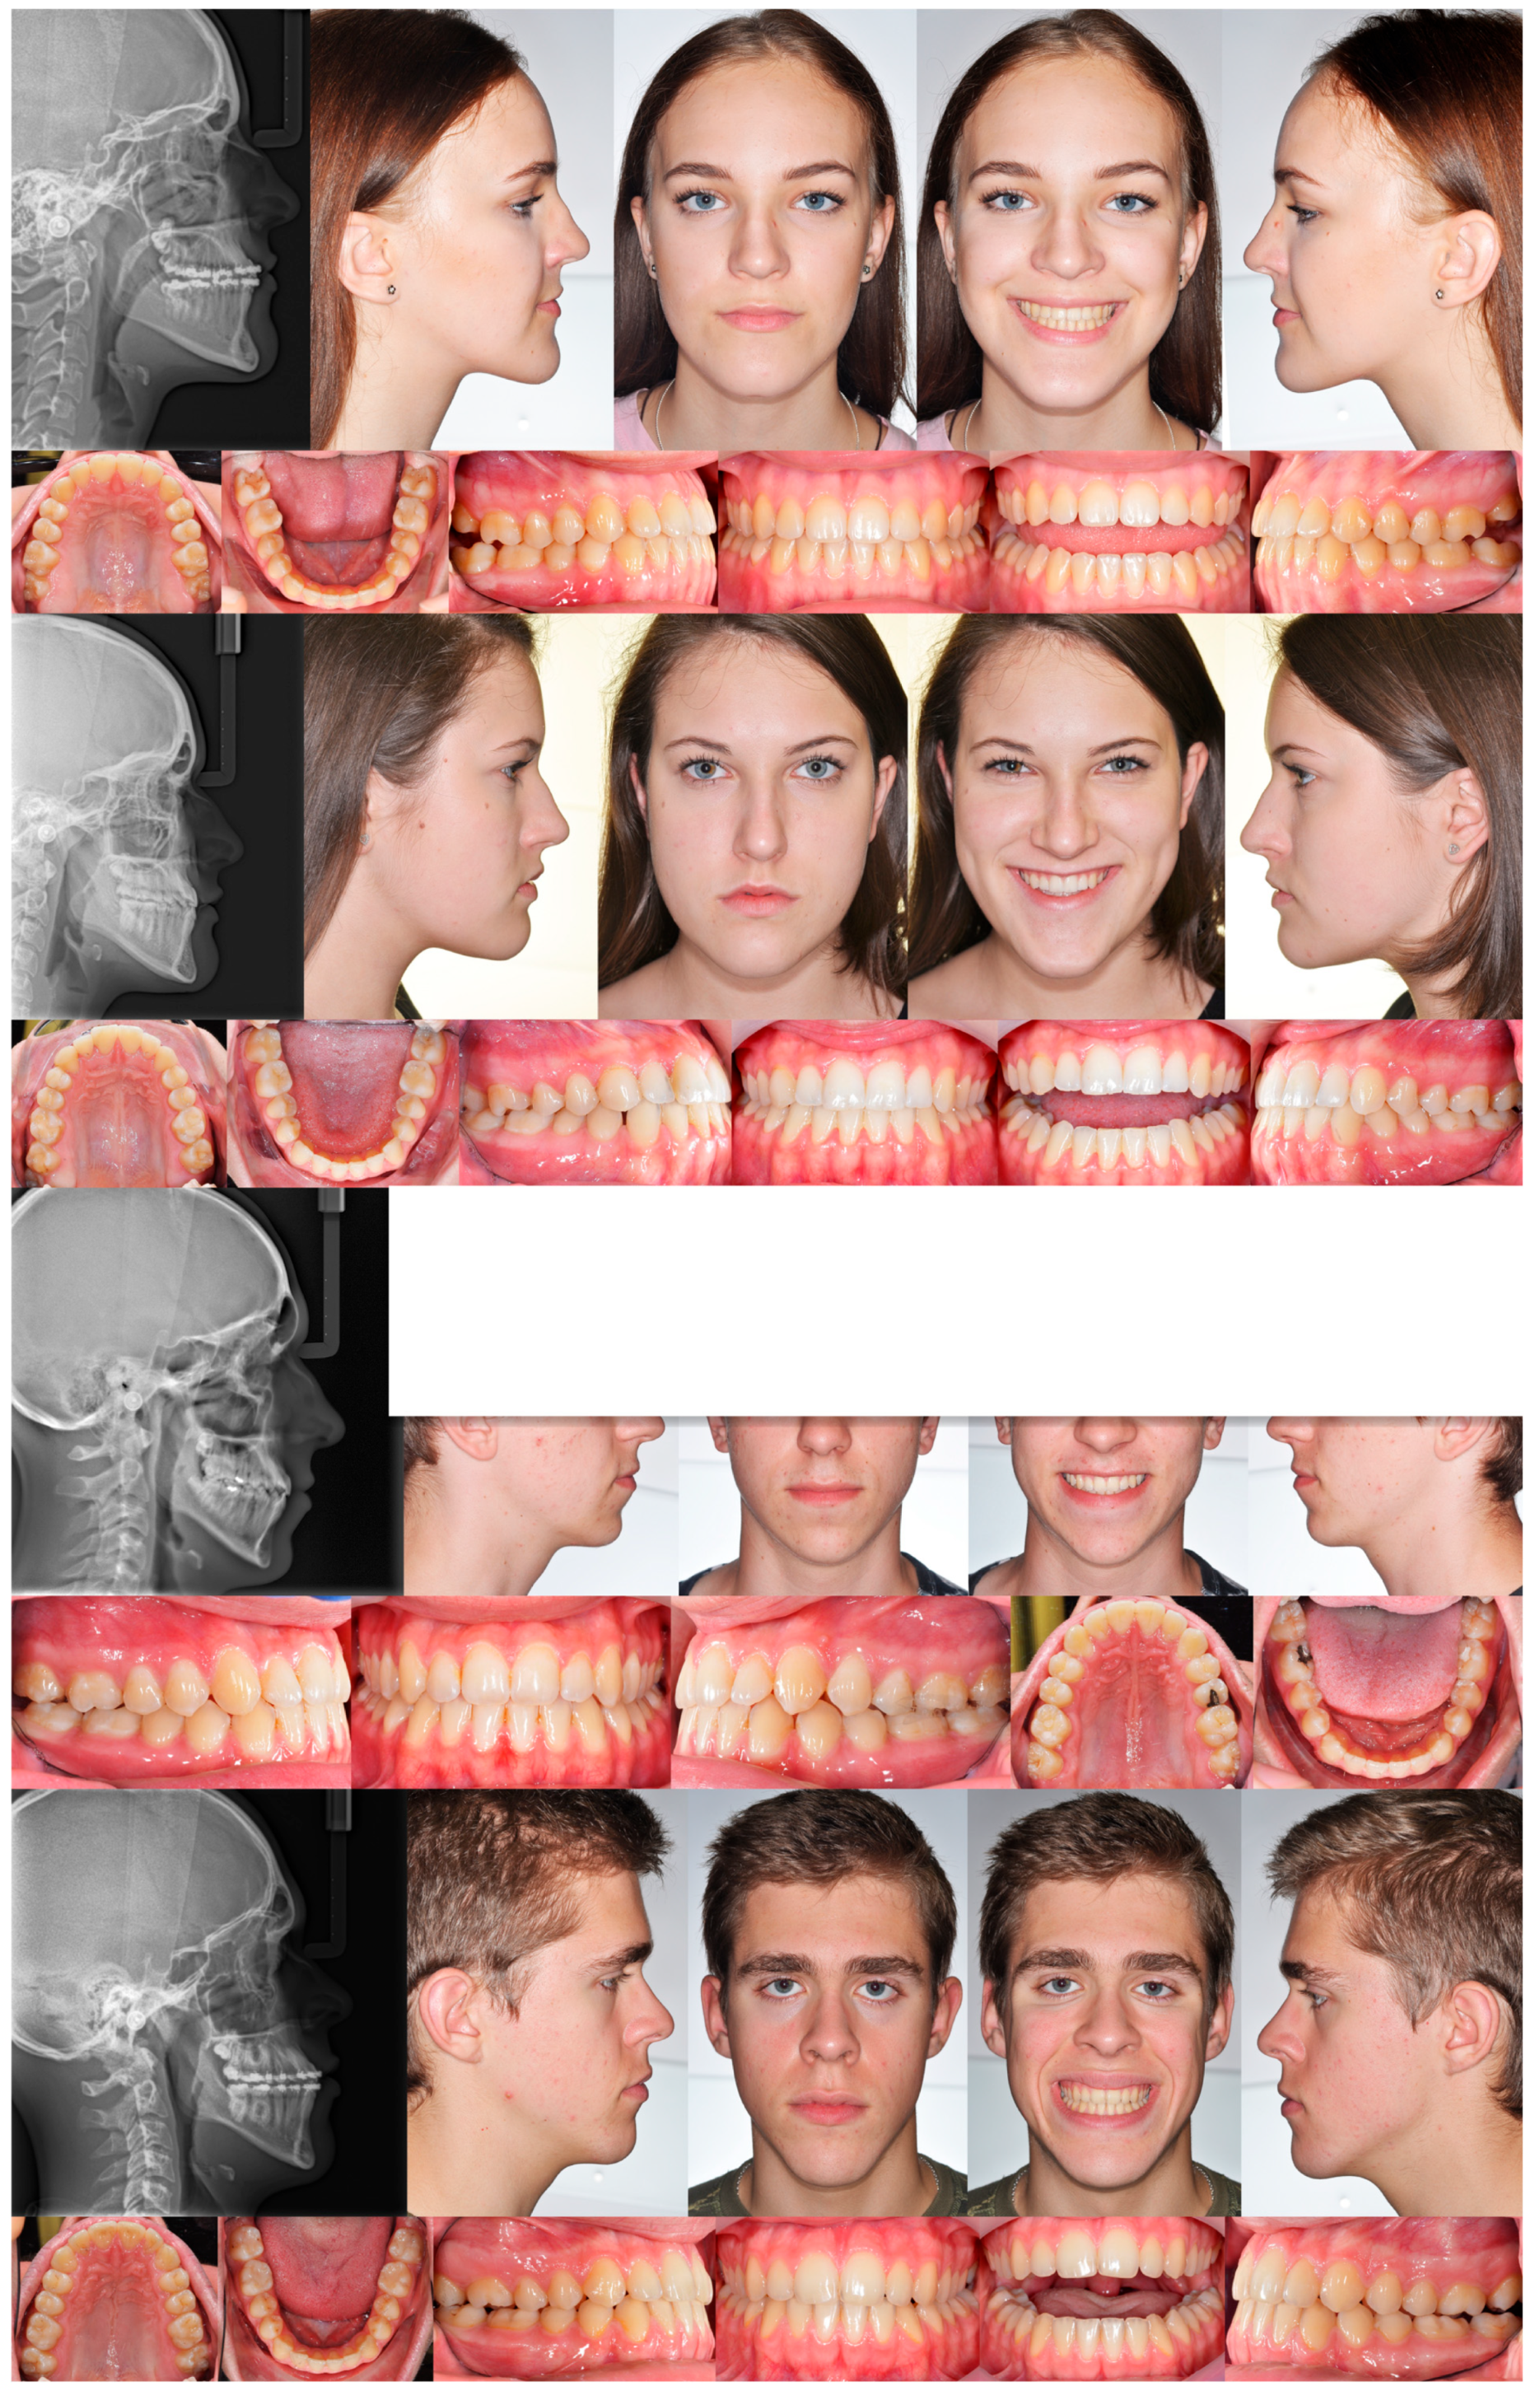

3. The Results of the Treatment